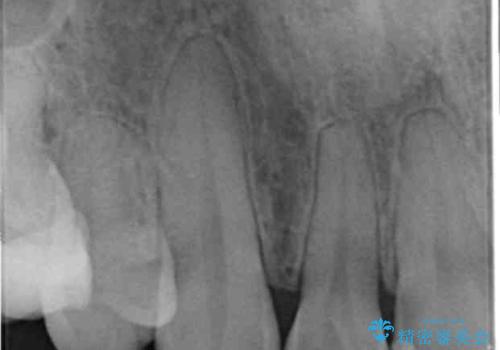

- K-POP(Kポップ)アイドルのような歯にしたいと希望され来院された患者様です。

矯正を途中でやめてしまったとのことで、歯に矯正の接着材が残っており着色も顕著でした。

奥歯の咬合面にはレジンが盛られた状態でした。

見た目と咬み合わせを改善するため、セラミッククラウンによる治療を行いました。

クラウンの種類:オールセラミッククラウン スタンダード